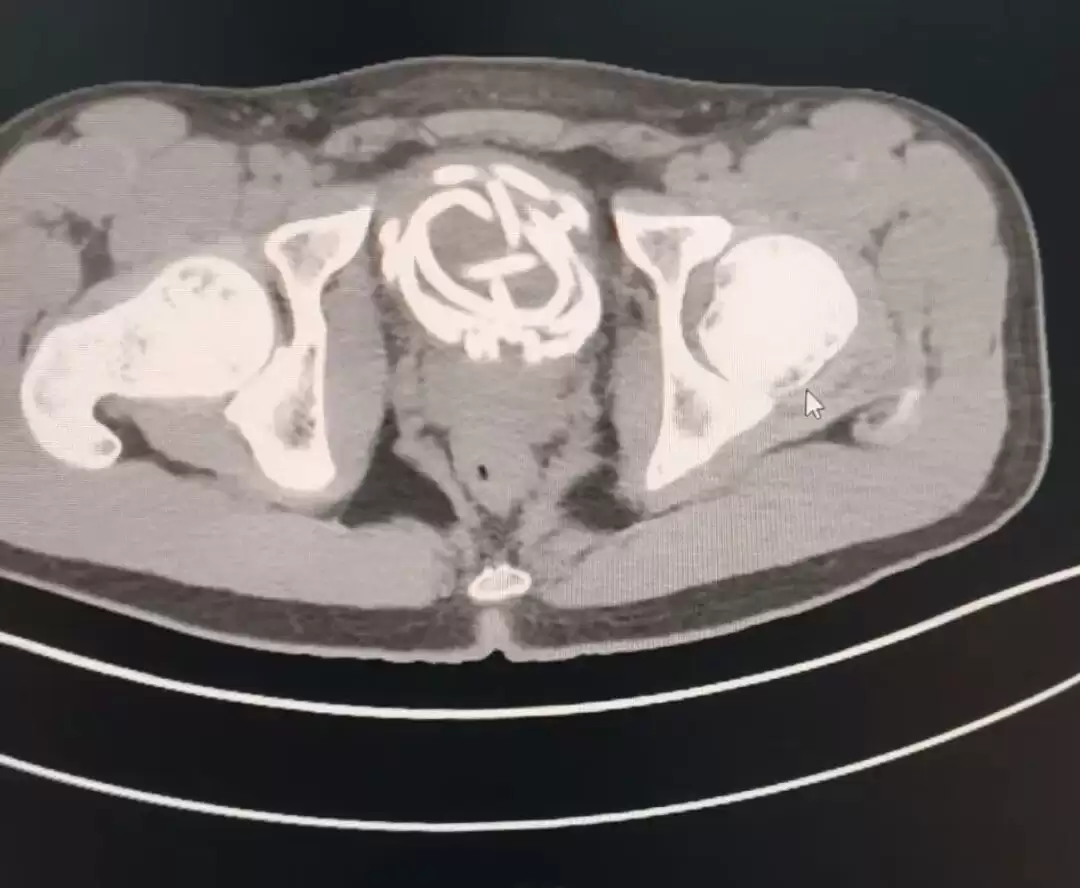

近日,扬州大学附属医院泌尿外科接诊了一名17岁高中男生,他因为好奇将跳绳的橡胶绳插入尿道,跳绳在膀胱内打结盘曲无法取出,并引发严重尿道感染,医生通过紧急手术,才成功取出跳绳。

(患者医学影像,图源扬州大学附属医院)

据了解,这名男生因一时好奇,将橡胶跳绳插入尿道,无法取出,随后出现剧烈疼痛、排尿困难等症状。医生立即为患者进行相关检查。检查结果显示,跳绳已经在膀胱内打结盘曲,由于滞留时间较长,患者尿道已出现严重感染并形成脓胎,如果不及时手术,可能引发更加严重的并发症。

在手术过程中,医生看到患者尿道黏膜因为异物刺激已经布满脓苔,跳绳相互缠绕,形成难以解开的死结。为最大程度减少创伤,医生团队采用腹腔镜下膀胱切开异物取出术,通过微小穿刺切口,在腔镜直视下将打结跳绳剪断后分段取出。手术创伤小、出血少、恢复快,最大限度保护了患者泌尿功能。术后,医院联合儿外科进行抗感染等对症治疗,目前患者病情平稳。